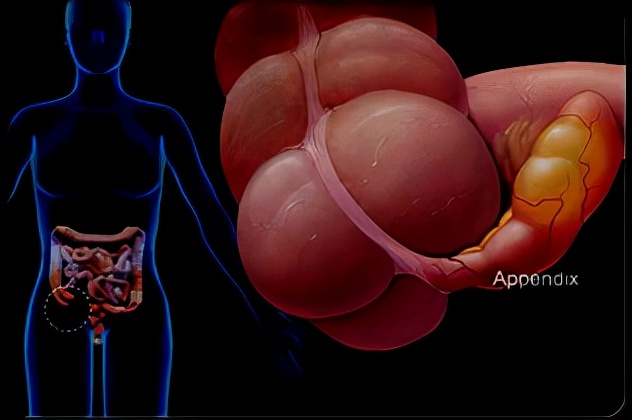

阑尾炎

(一)阑尾的解剖和生理 1.解剖(重点关注与外科密切相关的) 1)盲管,长5~10cm,直径0.5~0.7cm,起自盲肠根部,为三条结肠带的汇合点。

2)体表投影: 右髂前上棘与脐连线的中外1/3处,称麦氏(McBurney)点。是阑尾手术切口的标志点。

位置变异 很大,最常见(2/3)盲肠内侧。 阑尾尖端指向: ①回肠前位; ②回肠后位; ③盲肠外侧位; ④盲肠后位; ⑤盲肠下位; ⑥盆位。

3)阑尾动脉: 无侧支的终末动脉 ,血运障碍时易发生阑尾坏死。 4)阑尾静脉: 最终 汇入门静脉 ,当阑尾感染时,菌栓脱落,引起 门静脉炎和细菌性肝脓肿 。

5)阑尾神经: 由交感神经纤维经腹腔丛和内脏小神经传入,其传入的脊髓节段在 第10、11胸节 。 ①当急性阑尾 炎发作时—— 脐周牵涉痛 ,属内脏性疼痛(迟钝、模糊、定位不明确); ②当炎症累及腹膜时——躯体感觉性痛(敏感、定位准确)。 临床表现为 转移性右下腹痛 。

2.阑尾的生理 阑尾黏膜能分泌黏液; 深部的 嗜银细胞是产生阑尾类癌的组织学基础。 阑尾壁内有丰富淋巴组织。

(二)病因和病理类型 1.病因 (1) 阑尾管腔阻塞:淋巴滤泡增生 、粪石、异物、肿瘤等。 (2)细菌入侵:G-杆菌及厌氧菌。 (3) 阑尾先天畸形。